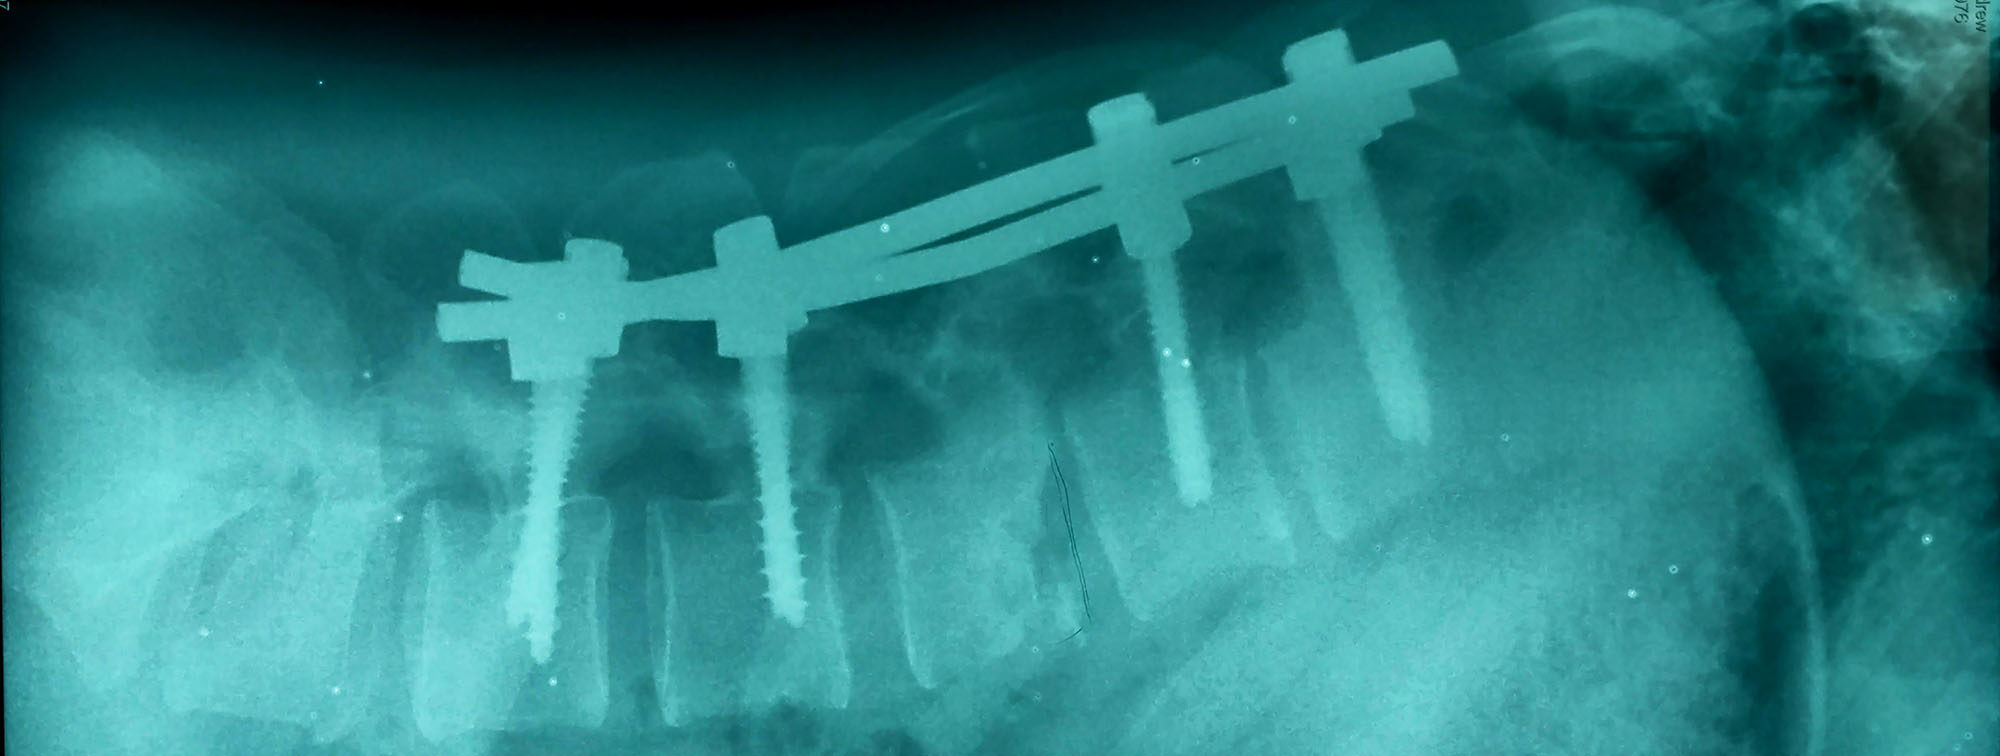

Fluoroscopic image of titanium rod construct with broken rod noted on Titanium Rod In Back Broke Screws, plates, rods, and other types of spine hardware are made of incredibly strong and sturdy materials (usually titanium and/or composites). But what happens when hardware breaks or gets infected? Though it is unlikely, it is possible for spine hardware to break after an operation for several reasons. First, we will conduct an imaging scan to confirm the fracture or. Titanium Rod In Back Broke.

Fluoroscopic image of titanium rod construct with broken rod noted on Titanium Rod In Back Broke In this article, we will talk about how to identify broken hardware in the spine, and what to do if you experience a broken rod or other. It is unlikely for the rod to. Spinal fusion hardware, like rods, screws, and plates, is often used in scoliosis surgery and can sometimes break or need to be. Even so, breakage does. Titanium Rod In Back Broke.

Fluoroscopic image of titanium rod construct with broken rod noted on Titanium Rod In Back Broke Many spine procedures use hardware like plates, screws and rods to stabilize your spine. The first thing to do is to recognize symptoms that may suggest your hardware is no longer providing support. The rod is just a solid metal rod. They are made to be long lasting and resist breaking. Even so, breakage does sometimes occur. It is unlikely. Titanium Rod In Back Broke.